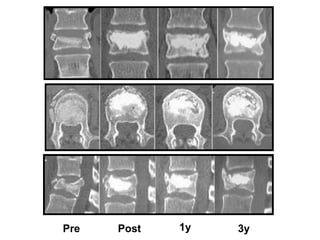

Vertebra Plana

Pre Post 1y 3y

Kyphoplasty